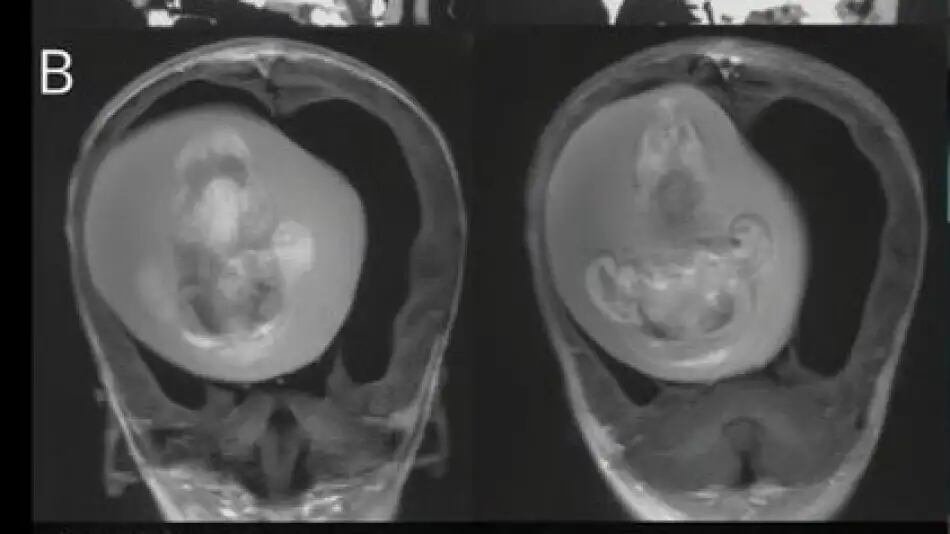

Un hecho poco común y sorprendente tuvo lugar en China, donde médicos lograron extraer un feto de la cabeza de una niña de un año de edad. El caso se conoce como “Fetus-in-fetu” o “gemelo parásito” y solo se ha documentado en 18 casos en todo el mundo dentro del cráneo.

El feto extraído, que medía alrededor de cuatro pulgadas de largo, había desarrollado extremidades superiores, huesos e incluso uñas, lo que demostró que había continuado su crecimiento en la cabeza de la niña durante meses. Los médicos explicaron que el feto estaba presionando contra el cerebro de la niña, lo que le causaba esos problemas.

Según los especialistas, el feto logró sobrevivir tanto tiempo porque ambos compartían el suministro de sangre. El caso fue publicado en la revista Neurology de la Academia Estadounidense de Neurología. Actualmente, se desconoce si la niña tendrá secuelas a futuro.